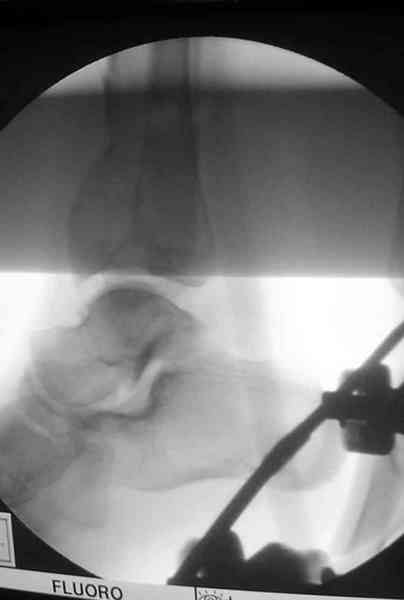

Дистрагированные лигаментотаксисом костные фрагменты иногда организуются в нужном направлении и во время операции облегчается репозиция отломков.

Дополнительные ренгенограммы после дистракции и

обязательная комьютерная томография дают возможности разузнать топографию расположения фрагментов, что немаловажно для планирования хирургического доступа.

Показатель готовности к операции считается когда

“wrinkle probe” на конечности положительная, то есть образования морщинок на коже конечности между двумя пальцами доказывает отсутствия отека, иначе первично невозможно закрыть рану.

Открыто или закрыто - это уже зависит от опыта и

наличия материала. Минимальным аппаратом Илизарова или одним из Contoured Medial или Antero-Lateral Locking Plate из лимитирванного доступа не имеет значения, но самое главное необходимо добиться репозиции сустава.

Здесь выставлена пара случаев перелома пилона, оба

случая леченные этапным наружным фиксатором.